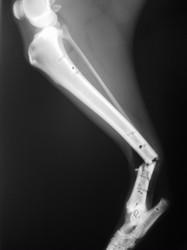

Fijación Externa

PRÁCTICAS CURSO DE FIJACIÓN EXTERNA PERFECCIONAMIENTO.

Híbrido.